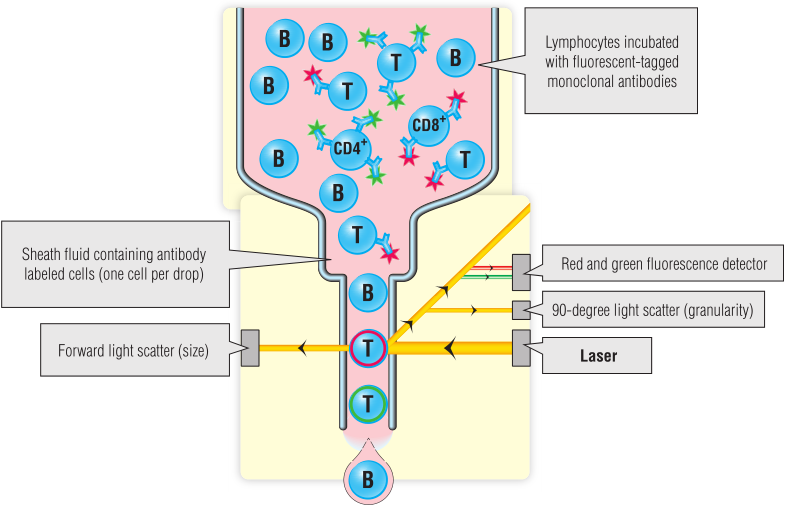

流式细胞术是一种用计数表达抗原的细胞的技术。这些细胞被细胞表面抗原特异性抗体染色。抗体被偶联到特定的荧光试剂,如FITC(还有其他几种不同颜色的荧光可供选择),然后通过流式细胞仪。染色细胞的数量可以计数,例如CD4+T细胞的数量(Fig 5.7;另一个例子见第35章)。

Fig 5.7 流式细胞仪“散点图”

BOX 5.3 临床诊断实验室新技术–荧光微球免疫分析

一种被称为Luminex xMAP技术的新诊断测试方法,似乎非常有价值,特别是在小体积样本上进行多项测试时。这项技术利用了酶联免疫吸附试验(ELISA)和流式细胞术两个方面。本质上,聚苯乙烯微球内部用两种荧光染料进行颜色编码,这两种染料可以在激光照射后检测到。通过混合不同的染料,最多100颗珠子中的每一颗都可以被赋予一个独特的身份(“光谱信号”),这可以在流式细胞仪中检测到(参见Fig 5.7)。每颗珠子还可以涂上不同的化合物,如抗体、寡核苷酸和酶,这些化合物可以从测试样本中收集分子。通过使用带有不同颜色荧光报告标签的夹心法(如Fig 5.11所示),可以用第二个激光测量化合物(例如,肝炎病毒抗体)的量。微球溶解在微滴定孔或试管中,并且多个珠子可以存在于单个容器中。每一颗珠子都可以用不同的反应物衍生化,一组100颗珠子可以分析多达100种不同的化合物。珠子在液体中被输送到分析仪中,并受到激光照射,很像流式细胞仪中的单个细胞(见Fig 5.7)。这项技术可以用来在很短的时间内从少量的样品中进行多项测试,称为多重测试。结果表明,该检测方法灵敏、特异,与ELISA等其他检测方法相比具有一定的优势。